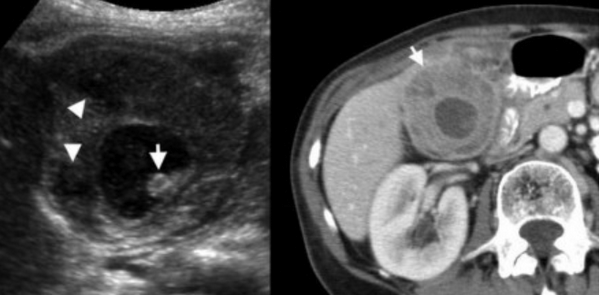

УЗИ и КТ желчного пузыря. Ксантогранулематозный холецистит. Слева на УЗИ визуализируется (помечено стрелками) утолщение стенки желчного пузыря с интрамуральным включением и с камнем в просвете органа. Справа на КТ выявляется утолщение стенки с гиподенсными включениями.

Выше представлено КТ пациента 71 года с ксантогранулематозным холециститом. Постконтрастное КТ. Визуализируется утолщение стенки желчного пузыря с включениями, которые соответствуют абсцессу или фокусам воспаления.

КТ желчного пузыря/Рак желчного пузыря

Наиболее часто встречаемый рак желчного пузыря является карцинома. Карцинома желчного пузыря занимает пятое место по частоте встречаемости среди раков желудочно-кишечного тракта. Чаще его обнаруживают случайно (в 2% случаях) при гистологической проверке после холецистэктомии. Карцинома желчного пузыря выявляется на последних стадиях заболевания так, как себя не проявляет клинически на ранних. Специфических признаков при карциноме желчного пузыря также нет. Рак может поражать желчный пузырь диффузно, целиком стенку или пристеночно. Карцинома желчного пузыря имеет схожую картину с ксантогрануломатозным холециститом, но при постановке диагноза радиологу помогают такие находки:

УЗИ (слева) и КТ (справа) желчного пузыря. На УЗИ ярко выраженное утолщение стенки желчного пузыря (указаны белыми стрелками). Множественные камни в просвете желчного пузыря (указано стрелкой). Компьютерная томография с контрастным усилением. На КТ визуализируются утолщение стенки с внутристеночными гиподенсными включениями. На КТ также выявлено, что процесс распространился на печень (указано стрелкой).